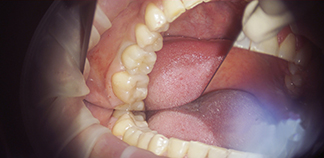

До лечения

Жалоба на плохое состояние нижних зубов.

Как лечили

Пролечен кариес под микроскопом и установлены импланты. Проведена хирургическая пластика десны. Протезирование коронками из диоксида циркония.